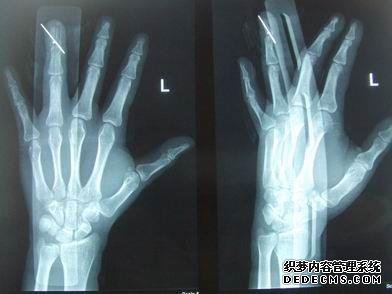

锤形是指伸肌腱破裂的症状之一。所谓的撕裂骨折是指在肌腱连接处的肌腱断裂。屈曲仍然可以稍微延长。这种运动是由于骨epi粘连。2.神经肌肉关节效应,三月骨折,手术治疗,远端远端指骨细骨缆,伸肌腱被发现可将纽扣固定在指尖一侧,修复后拔下电缆。

左手的小指占左手的5-8%,因此在受伤3个月后,小指的间隙为0.5 mm,手术取决于需要和要求。

我不知道sprint最初放在哪里。它放置在伸出位置,即小指尖尽可能延伸的位置。